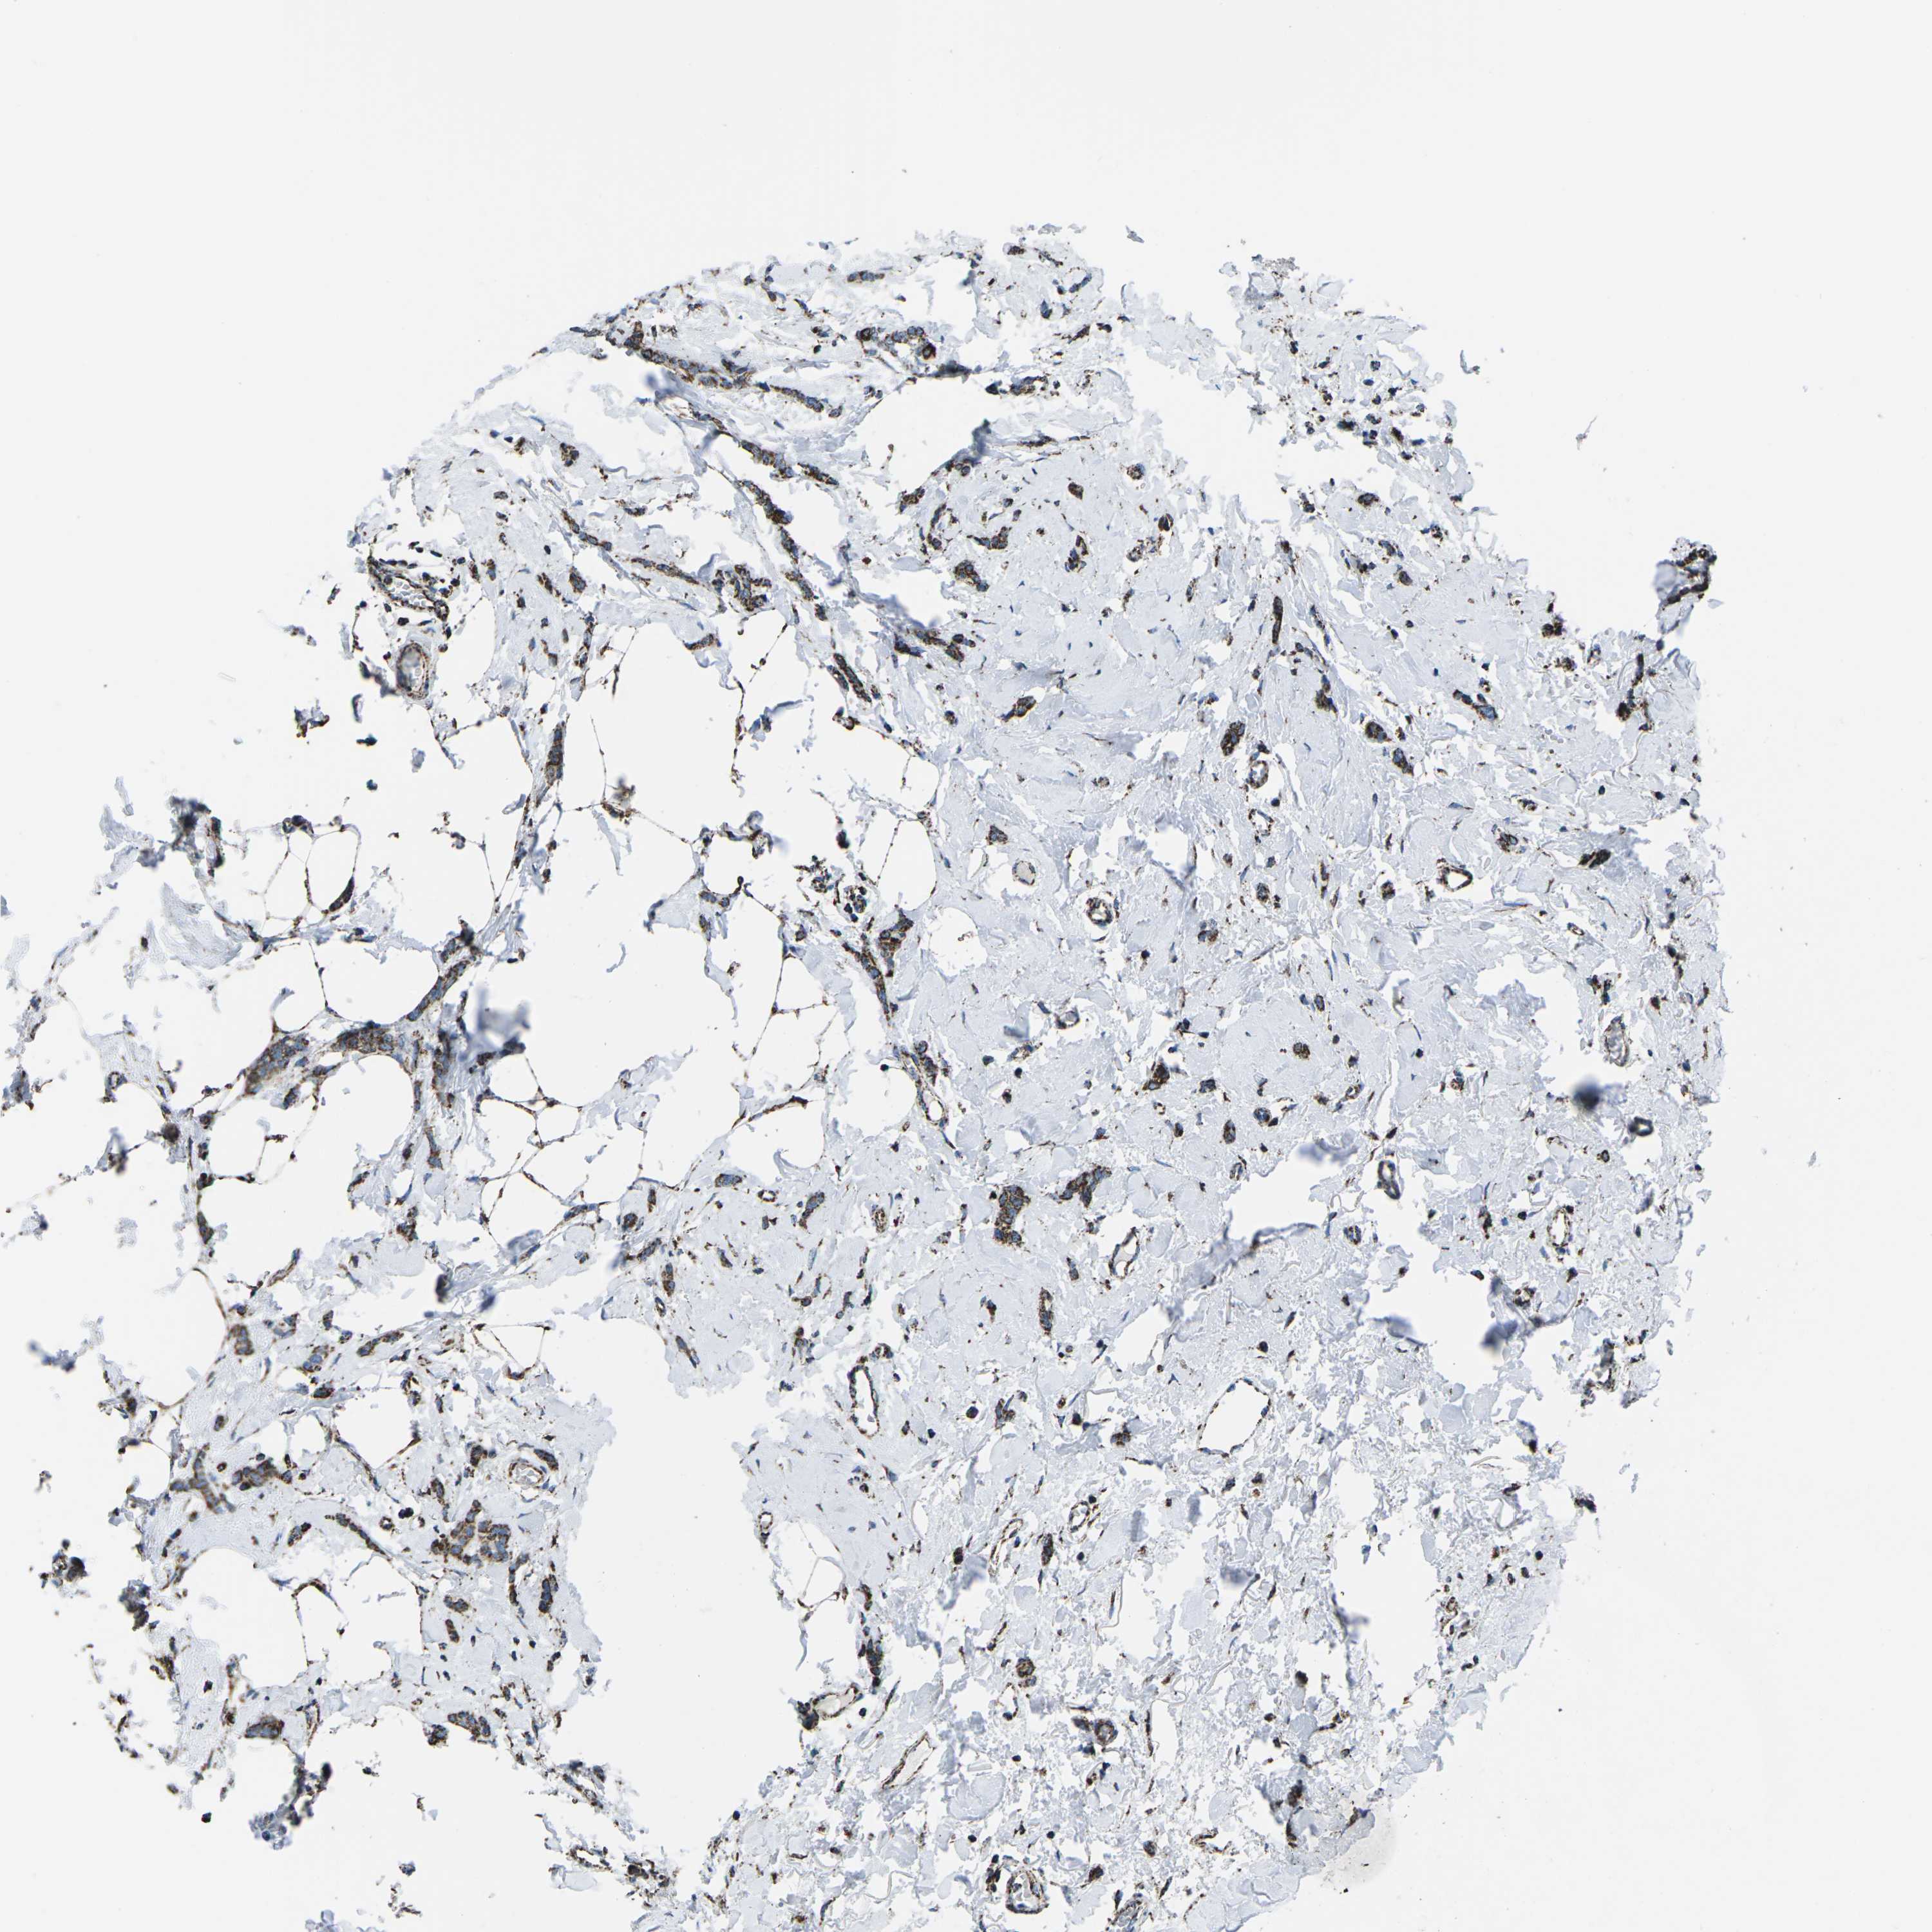

CANCER BREAST CANCER Show tissue menu

BRCA TCGA BRCA VALIDATION PROTEIN EXPRESSION